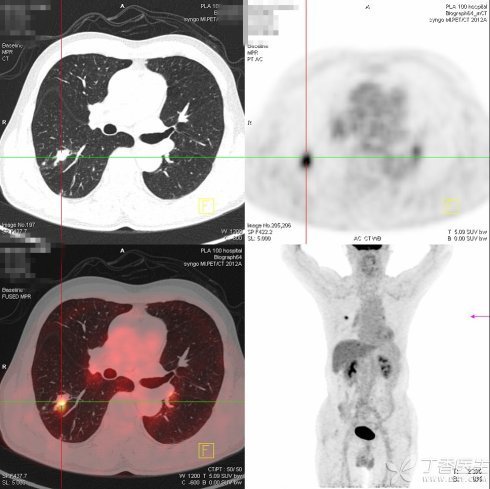

这个理论是被实验证明的。最重要的实验,也是该理论最伟大之处,就是成就了 PET-CT 技术在临床检查的应用。

它的中文名叫「正电子发射型计算机断层显像」,利用癌细胞比正常细胞需要更多葡萄糖的特点,将葡萄糖分子打上机器能够辨别的标记,然后将这些葡萄糖打进患者血液里,带着放射性核素的葡萄糖会被癌细胞大量摄取,在癌细胞内浓聚。医生通过特殊的仪器就能看到人体内某些组织、部位「亮」了,而这些发亮的组织、部位往往就是癌症病灶。